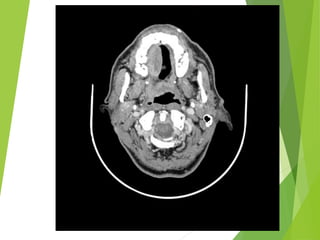

Estudios de imagen

20 de Marzo 2013

Estudios de Imagen:

-TAC de cuello simple y contrastado

20 de Marzo2013 Estudios de Imagen: -TAC de cuello simple y contrastado